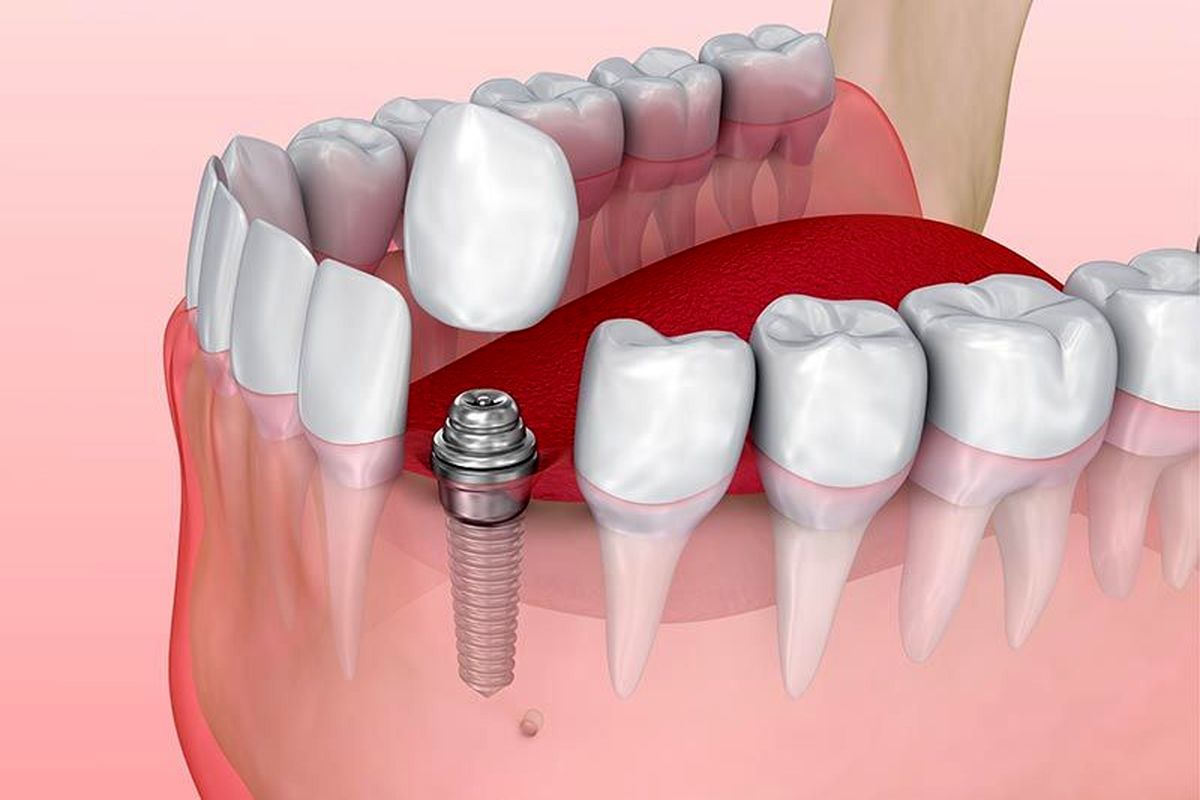

کاور اسکرو F&B پیچ کوچک یا قطعه ریزی هست که سر ایمپلنت بسته می شود تا مواد غذایی و لثه یا بافت نرم داخل مرکز ایمپلنت که سوراخ توخالی است، نفوذ نکند. در واقع اگر بخواهیم تشبیه کنیم کاور اسکرو مثل بوش سر لوله است که برای این که آب از لوله بیرون نیاید، سر لوله را با بوش پلمپ می کنیم. کاور اسکرو هم همین کار را می کند.

پس از قرار دادن فیکسچر در فک، کاور اسکرو سطح داخلی فیکسچر را می پوشاند. مزیت کاور اسکرو این است که در عمیق زیرین قرار میگیرد و از طریق لثه ها مهر و موم می شود و اجازه می دهد زخم بدون سردرد بهبود یابد و خطر عفونت به حداقل برسد. کاور اسکرو در مواردی مانند جراحی پیوند استخوان و سینوس لیفت نیز استفاده می شود.